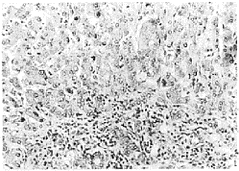

图 1 免疫组化法检测HSP90β在人胃炎组织中的表达,HSP90β位于腺上皮细胞质

Fig 1 HSP90β expression in human gastritis tissues.

HSP90β is localized in the plasma of the glandulous epithelial cells ×200

图 2 免疫组化法检测HSP90β在人胃癌组织中的表达,HSP90β位于癌细胞质

Fig 2 HSP90β expression in human gastric cancer tissues.

HSP90β is localized in the plasma of the cancer cells ×400